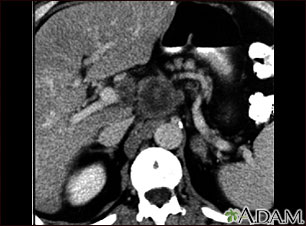

A CT scan of the upper abdomen showing a tumor (pancreas carcinoma) in the head of the pancreas, seen here in the middle of the picture.